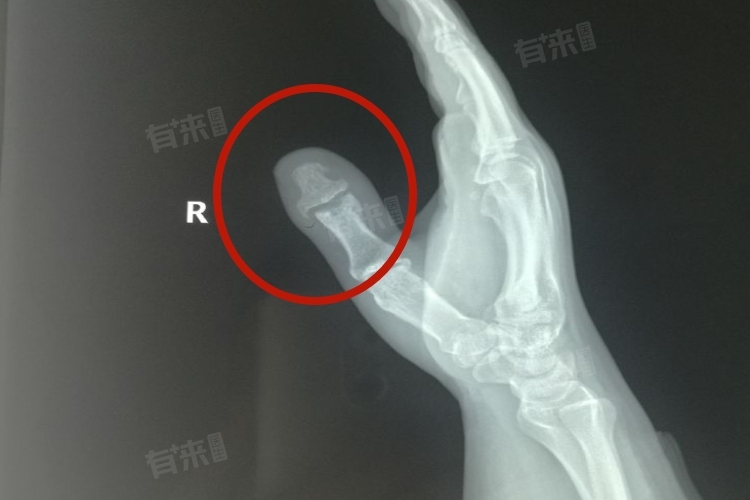

4、影像学检查

- X线检查:是判断手指是否骨折的重要手段。通过X线片,可以观察到手指骨骼的结构和形态,判断是否存在骨折以及骨折的具体位置和移位情况。

- CT或核磁共振检查:在某些情况下,为了更准确地判断骨折情况,可能需要进行CT或核磁共振检查。